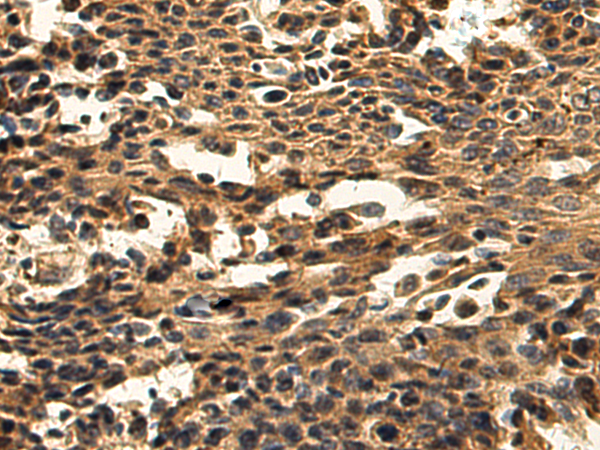

The image is immunohistochemistry of paraffin-embedded Human ovarian cancer tissue using (DNAJB11 Antibody) at dilution 1/220. (Original magnification: ×200)

The image is immunohistochemistry of paraffin-embedded Human lung cancer tissue using (DNAJB11 Antibody) at dilution 1/220. (Original magnification: ×200)